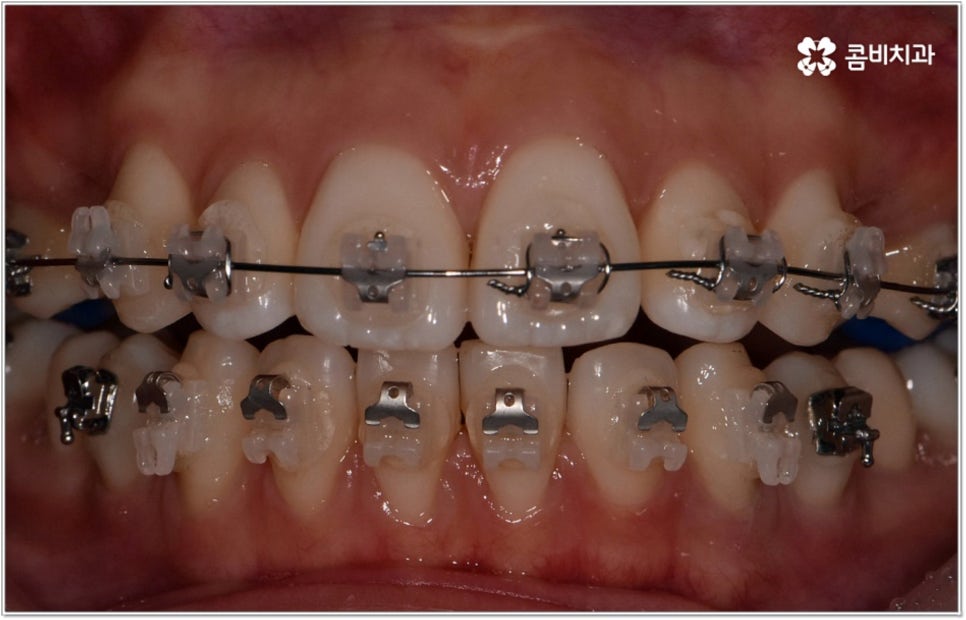

청소년기는 교우 관계에 영향을 많이 받고 외모에 민감할 때라 교정기에 대한 반감이 있을 수 있으나 바로 이때가 치아 이동에 있어 매우 중요한 시기이므로 제대로 이해할 수 있도록 차근차근 설명해 줄 필요가 있는데요. 12~15세 사이, 즉 초등학교 고학년에서 중학교 저학년 사이가 유치에서 영구치로 거의 다 교체되고 잇몸뼈가 계속해서 성장하는 나이이기 때문에 상악과 하악의 균형잡힌 발달을 유도하면서 부정교합을 바로잡고 치열을 가지런하게 만드는데 보다 빠르고 효율적인 만큼 가능하다면 이 시기를 놓치지 않는게 중요한 거예요. 물론 성인분들도 상황에 맞게 교정 치료를 진행할 수 있지만 부정교합의 종류와 정도에 따라 성장기 교정 치료를 진행하는 것이 좀 더 나은 케이스가 있으니 아이의 치열에 관심을 가지고 정확하게 알아보시는 것이 도움이 될 수 있습니다.

무리하지 않고 돌출입치아교정 과정을 진행하기 위해서는 먼저 꼼꼼한 검진 및 분석에 따른 철저한 맞춤 치료 계획 수립이 중요하다고 할 수 있는데요. 특히 3D CT 및 모르페우스 시스템을 통해 현재 아이의 치열이나 연조직, 상하악 관계 등을 자세히 살펴보고 안모 분석 후 교정 치료가 끝난 예상 모습을 시뮬레이션해서 보여주면 환아의 흥미를 유발하고 앞으로 진행될 사항에 대한 이해도를 높여줄 수 있어 긍정적인 영향을 줄 수 있으니 정밀 검진 장비를 갖추고 숙련된 의료진이 치료하는 치과에서 돌출입치아교정 과정을 진행하시길 권유드리고 있어요.